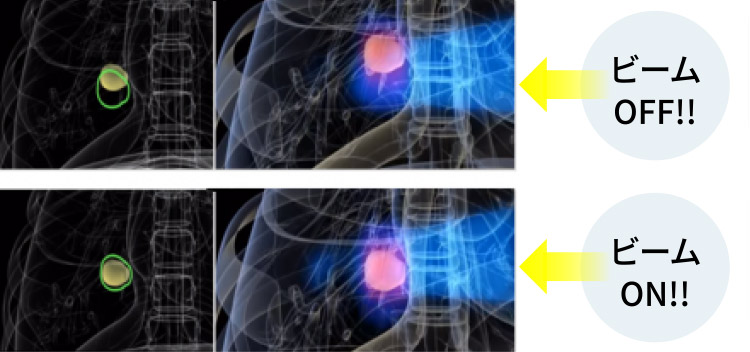

呼吸運動のある臓器では、病変に集中した照射野を正確に照射することが難しくなります。4D-CBCTでは内臓器の動きまでリアルタイムに観察し、ビームの再現性を⾼めます。

このNovalis TxのX線ビームを射出する開⼝部絞り(マルチリーフ)は2.5mmきざみで微⼩なものから40cmの広範囲までをカバーします。刻々と変化する⼈間の⾝体の動きに対応するため、3種類の画像誘導装置を備え、治療寝台上で体表の動きを⾚外線で、⾻格の動きをX線透視画像で、内部臓器の動きをCT横断像で把握し、コンピューター計画時との誤差を0.1mmの精度で位置座標を算出。算出したずれをロボット寝台が毎回、⾃動的に補正し精密な治療を実現します。また呼吸運動のリズムにあわせビーム発射を⾏う呼吸同期機能も備えています。従来機では頭部の定位放射線治療(ラジオサージェリー・ピンポイント照 射)で1mm以内の誤差を確保するためには頭蓋⾻のピン固定が必要でしたが、新型機では不要となりました。